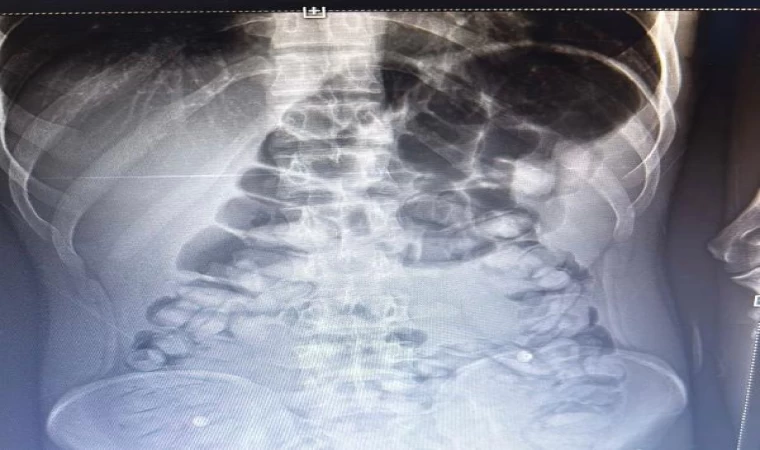

ERZURUM, (DHA)- ERZURUM'da, yolcu otobüsünde şüphe üzerine hastanede röntgeni çekilen yolcunun midesinde Afyon sakızı, tespit edildi. Yolcu, midesindeki 1 kilo 134 gram Afyon sakızını doğal yollarla çıkardı.

İl Emniyet Müdürlüğü Narkotik Suçlarla Mücadele Şube Müdürlüğü ekipleri, bir yolcu otobüsünde yaptığı denetimde, durumundan şüphelendiği yolcuyu hastaneye götürdü. Burada rdöntgeni çekilen yolcunun midesinde uyuşturucu tespit edildi. İlaç verilen yolcu, 1 kilo 134 gram Afyon sakızını doğal yollarla çıkardı.

Yolcunun midesinden 1 kilo 134 gram Afyon sakızı çıktı